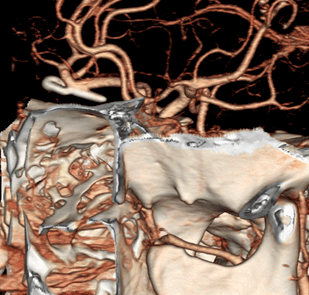

수술전 CT혈관조영술에서 전교통동맥의 비파열성 뇌동맥류 발견

혈관내 코일색전술 후 동맥류 내부에 코일이 들어가 있는 모습

뇌CT에서 뇌지주막하풀혈 소견이 보임

CT혈관조영술에서 우측 중대뇌동맥에 뇌동맥류 발견

결찰술후 시행한 CT에서 클립을 확인할 수 있음